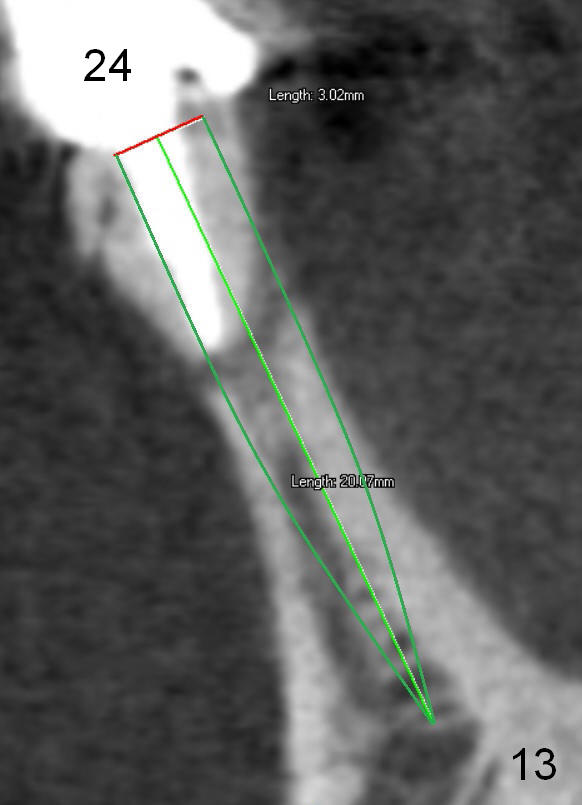

Fig.7 shows these two one piece implants immediately prior to cementation of the FPD (Fig.8). They are much more parallel to each other after prep, as compared to Fig.6. Fig.9 shows apparent bone growth around #24 implant (at the crest) 6,9 months post cementation and surgery, respectively. Orthodontic treatment will incorporate the fixed partial denture. Fig.10 shows that bone grows coronally (arrow) to cover 3 threads (from #6 thread to #3) at the site of #24 one year after functioning. There is mild buccal gingival infection involving #26 retainer. Preop CBCT is reviewed to determine whether it is related to potential thread exposure. It appears that at the sites of #24 (Fig.13,14) and 26 (Fig.11,12), 2.5 mm implant is more appropriate for the narrow ridge than 3.0 mm one. In fact, periimplantitis develops at #26 two years of absence of perio maintenance (because of atrial fibrillation with blood thinner; Fig.15, 3 years 7 months post cementation). Periimplantitis persists 4.5 months later. Although water pik is purchased, it is not used often because of low blowing force. If needed, remove the FPD atraumatically. Unwind the implant, clean the coronal threads with Titanium brush or remove the exposed threads and replant the implant with bone graft.